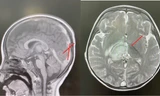

Trong nghiên cứu "Chất tạo ngọt không dinh dưỡng Erythritol ảnh hưởng xấu đến chức năng tế bào nội mô mạch máu nhỏ ở não" đã được công bố trên Tạp chí Sinh lý học ứng dụng, các nhà nghiên cứu đã thiết kế các thí nghiệm trong ống nghiệm để kiểm tra hậu quả của việc tiếp xúc với erythritol đối với chức năng nội mô não.

Các nhà nghiên cứu kết luận rằng, việc tiếp xúc với erythritol làm gián đoạn nhiều cơ chế quan trọng để duy trì sức khỏe nội mô não. Mặc dù kết quả chỉ giới hạn ở các tình trạng cấp tính trong ống nghiệm, nhưng những phát hiện này phù hợp với mối liên hệ dịch tễ học trước đây giữa erythritol và nguy cơ đột quỵ cao.